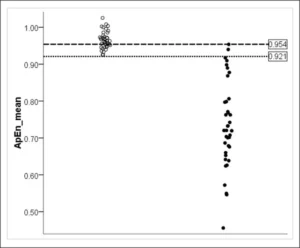

Leggi di Più..Isolamento Funzionale all’Interno della Corteccia Cerebrale nello Stato Vegetativo: un Metodo non Lineare per Prevedere gli Esiti Clinici

Lo studio utilizza l’analisi non lineare dell’EEG per valutare la...